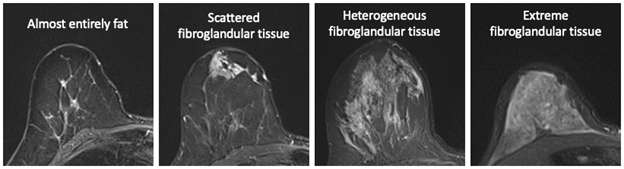

- Review MIP images to assess background parenchymal enhancement and suspicious enhancing regions. Assess amount of fibroglandular tissue.